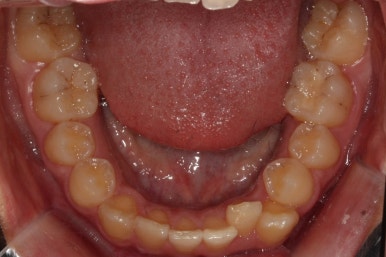

부산교정전문의 키다리아저씨치과에 처음 내원하셨을 때 당시의 입안 모습입니다.

윗니 뿐만 아니라 아랫니 부위에도 덧니가 관찰됩니다. 다른 앞니, 어금니 부위도 약간 삐뚤한 부분이 보입니다.